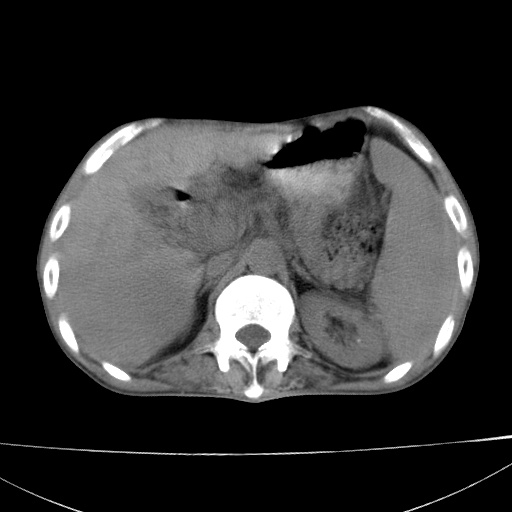

患者 男  41岁,右上腹痛伴腹泻10天,8年前有乙肝,本次b超查肝右叶占位来做ct ,请会诊!

肝硬化\\脾大\\门静脉高压,胃底静脉曲张可能性大.肝右叶肝癌肝内转移,建议增强.左侧小结石.

支持肝癌伴肝内转移,脾大,门静脉高压,胃底静脉曲张。

1)考虑肝癌;建议行ct增强扫描检查。2)脾大,门静脉高压,胃底静脉曲张。3)左肾小结石。

1)考虑肝癌及门脉瘤栓,建议行ct增强扫描检查。2)脾大,门静脉高压,胃底静脉曲张。3)左肾小结石。

结合病史;考虑肝癌。门静脉高压,脾大。胃底静脉曲张。

1)考虑肝癌;2)脾大,门静脉高压,胃底静脉曲张。3)左肾小结石。建议行ct增强扫描检查。